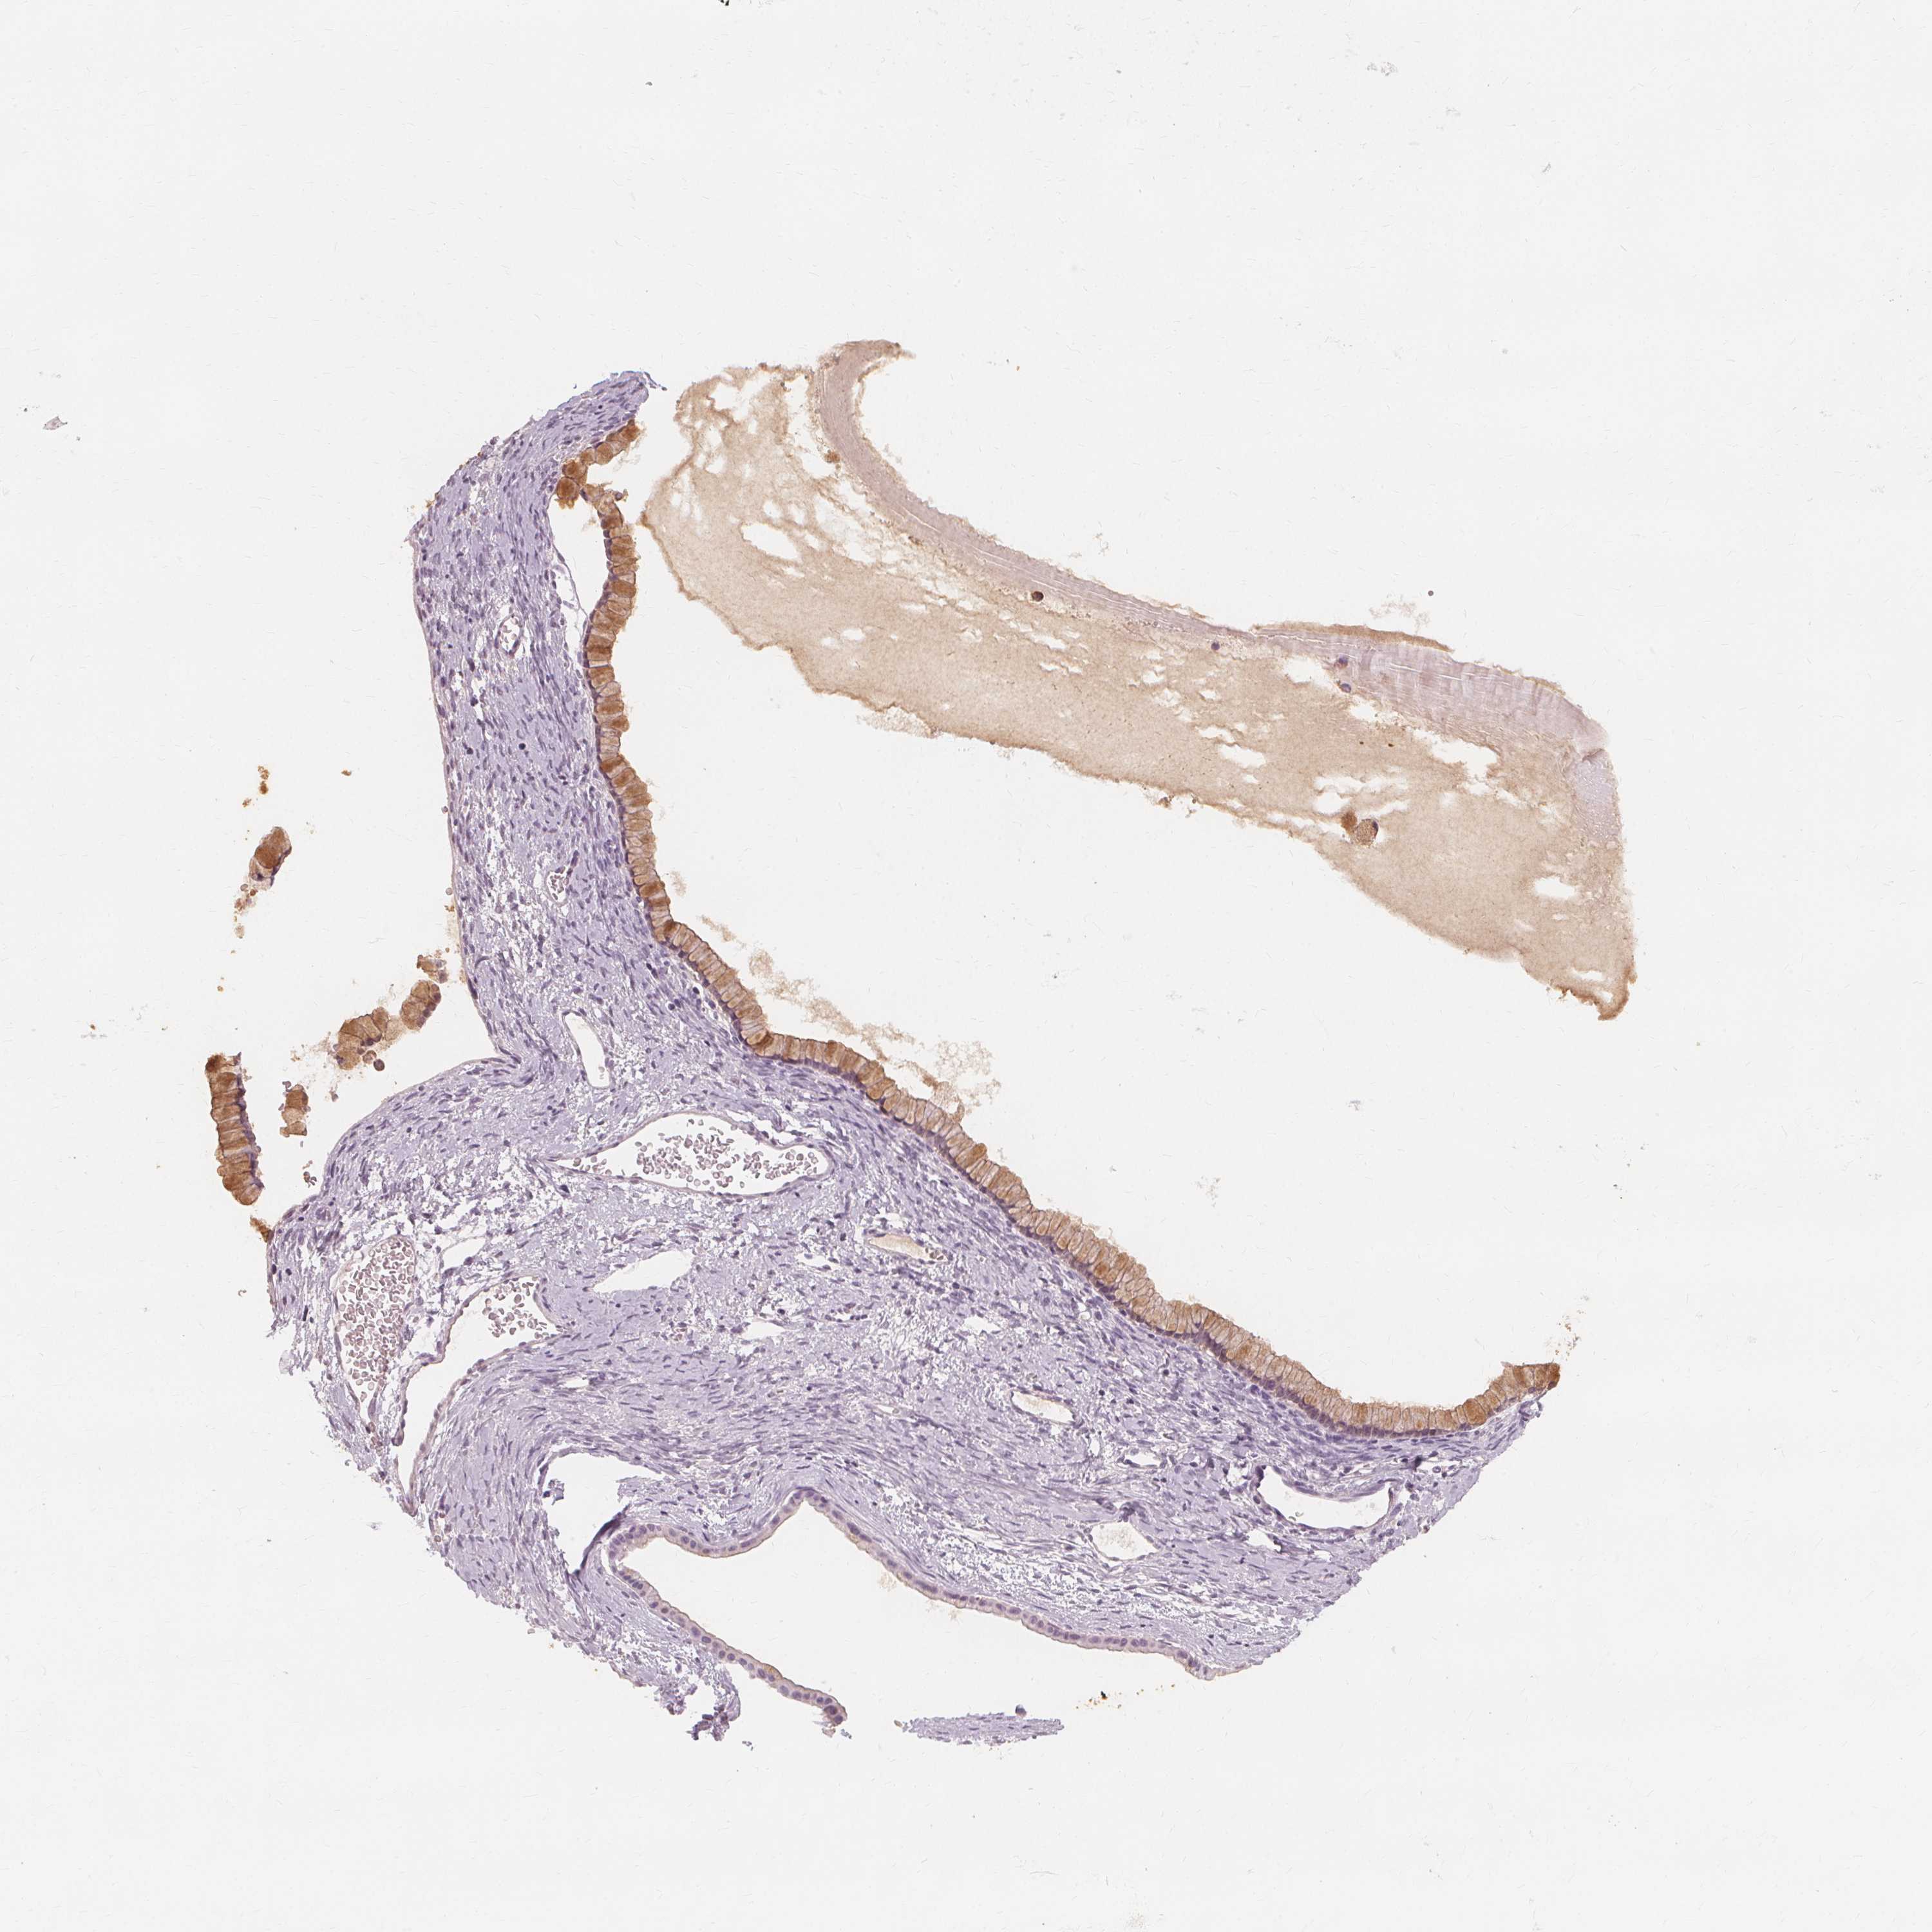

OVARIAN CANCER - Protein expressioni

A mouse-over function shows sample information and annotation data. Click on an image to view it in a full screen mode. Samples can be filtered based on level of antibody staining by selecting one or several of the following categories: high, medium, low and not detected. The assay and annotation is described here.

Note that samples used for immunohistochemistry by the Human Protein Atlas do not correspond to samples in the TCGA dataset.

Antibody stainingi

Antibody staining in the annotated cell types in the current human tissue is reported as not detected, low, medium, or high, based on conventional immunohistochemistry profiling in selected tissues. This score is based on the combination of the staining intensity and fraction of stained cells.

Each image is clickable and will lead to virtual microscopy that enables deeper exploration of all samples and also displays staining intensity scores, fraction scores and subcellular localization as well as patient and tissue information for each sample.

Antibody HPA003425

Antibody CAB002170

Cystadenocarcinoma, serous, NOS

Cystadenocarcinoma, mucinous, NOS

Carcinoma, endometroid